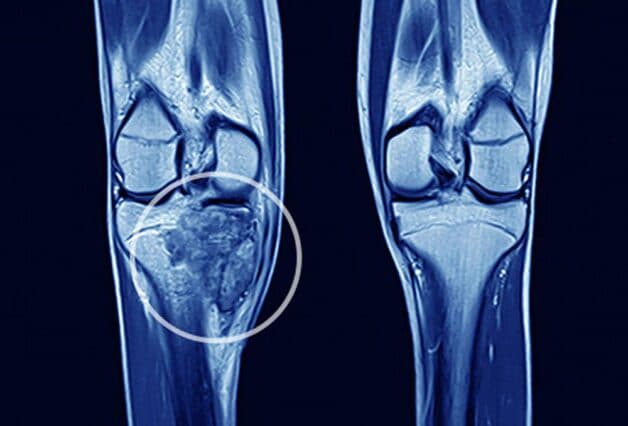

Ung thư xương hay u xương ác tính là căn bệnh nguy hiểm nhất trong số những bệnh lý về xương. Bệnh có khả năng di căn rất cao, khoảng gấp 3 đến 4 lần so với những loại ung thư khác.

Ung thư xương được xem là bệnh lý nghiêm trọng khi khối u hình thành ở xương hoặc ở các vị trí xung quanh của mô xương(sụn). Đây là bệnh lý thường gặp ở trẻ vị thành niên và người dưới 30 tuổi nhưng đa số có ít trường hợp người trung tuổi mắc bệnh.

– Sarcoma xương: Thường gặp ở thanh thiếu niên và trẻ em những vẫn có thể gặp ở người lớn với sự xuất phát từ đầu xương dài ở chân và tay.

– Sarcoma sụn: Thường xuất hiện ở xương chậu hoặc đùi của người lớn tuổi.

– Sưng và nổi cục u ở xương: Đây là dấu hiệu trong thời gian đầu của bệnh và khối u phát triển khiến cho những mô xương bị lồi ra ngoài. Nếu sờ vào khối u bạn có thể cảm nhận chúng lồi lõm bất thường.